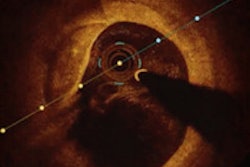

| Axial MR images of an 82-year-old symptomatic patient without cardiovascular risk factors. The patient suffered a stroke ipsilateral to the left carotid artery five days before the MRI examination. The arrowhead points to a complicated eccentric plaque that is hyperintense on time-of-flight (TOF) and T1-weighted images, indicative of intraplaque hemorrhage. Of note, no luminal stenosis in the ICA (asterisk) can be seen. The images illustrate that cerebrovascular events due to macroangiopathic carotid disease can occur in the absence of luminal stenosis. ICA = internal carotid artery, ECA = external carotid artery, VA = vertebral artery, PDW = proton density-weighted image. (Provided by Dr. Tobias Saam) |